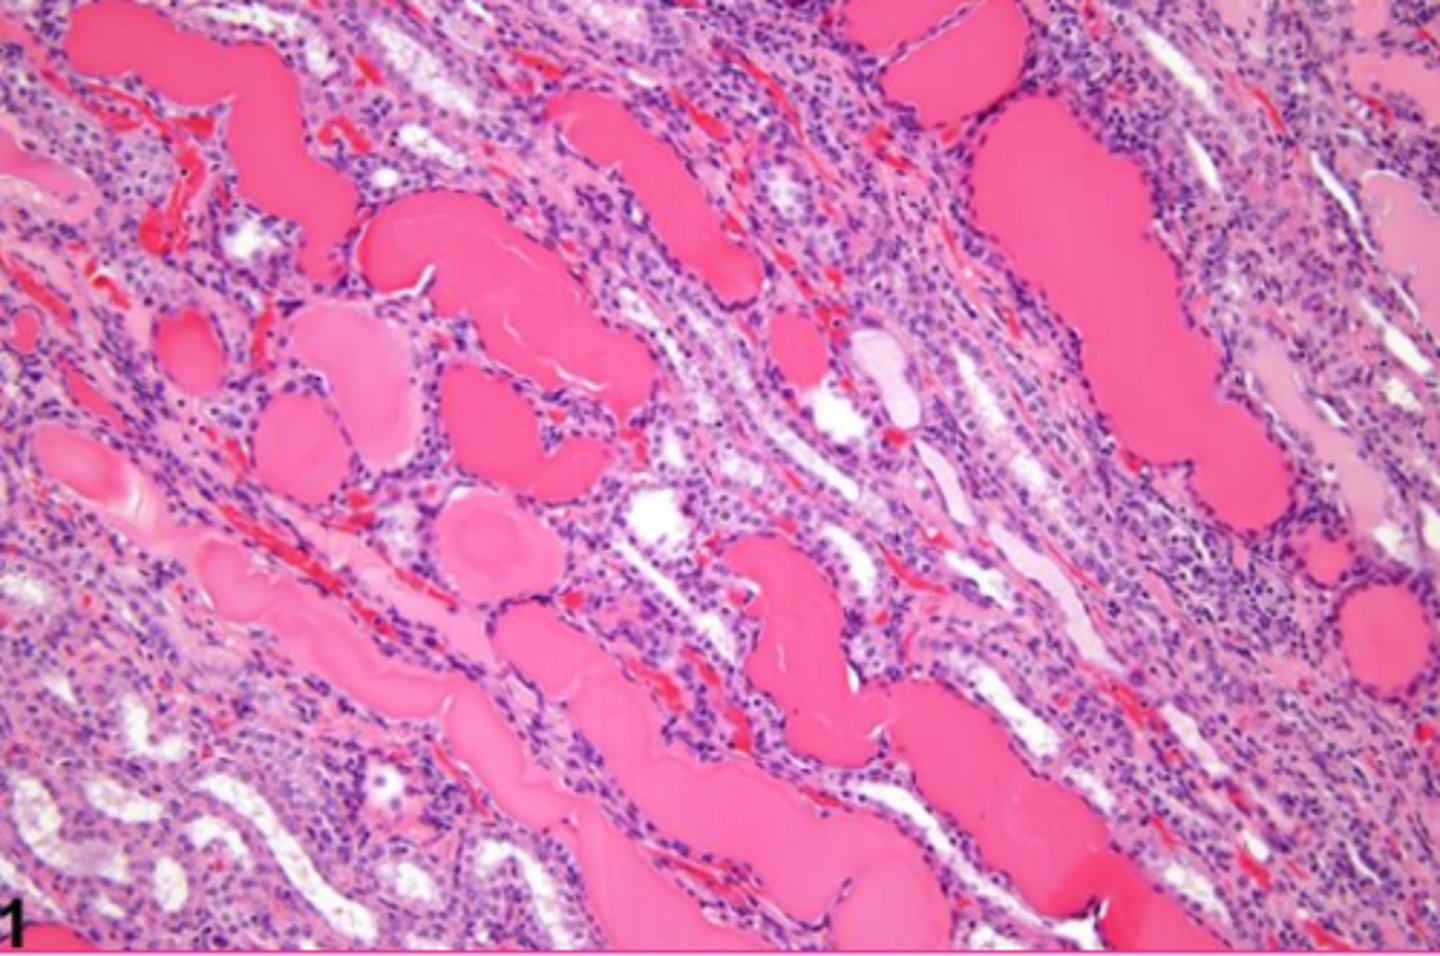

New cards

protein in renal tubules, serum/plasma in vessels, collagen fibers, thickened basement membranes, corpora amylacea

What are some examples of hyaline substances?